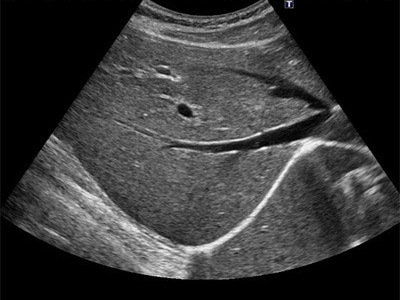

복부 초음파는 초음파(ultrasound)를 이용해 복부 내 장기들의 상태를 확인하는 비침습적 검사 방법입니다. 방사선을 사용하지 않아 인체에 해롭지 않고, 고통 없이 실시간으로 복부 장기들을 관찰할 수 있다는 점에서 가장 기본적이면서도 효과적인 진단도구로 평가받습니다.

초음파 탐촉자(Probe)에서 발생한 고주파 음파가 인체 내부 장기에 부딪혀 반사되며, 복부 초음파로 알 수 있는 것은 바로 이 반사파를 영상화해 간, 담낭, 췌장, 비장, 신장(콩팥), 방광, 대동맥, 림프절 등의 상태를 분석하게 됩니다.